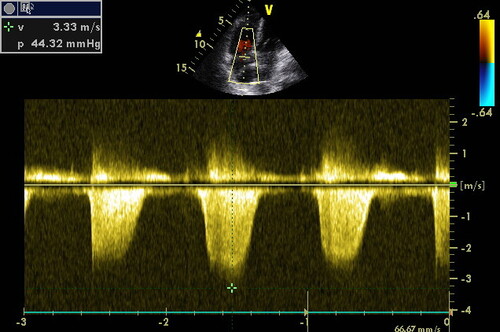

Лекция посвящена проблеме оценки легочной гипертензии. Существует классический подход к проведению эхокардиографического исследования у больного при подозрении на повышенное давления в малом круге кровообращения.

Мы обсудим все известные способы расчета максимального систолического, конечного диастолического и среднего давления в легочной артерии.

Лекция посвящена проблеме оценки систолической и диастолической функций правого желудочка.

Мы обсудим все способы расчета фракции выброса правого желудочка, способы оценки диастолы правого желудочка, причины их нарушения.